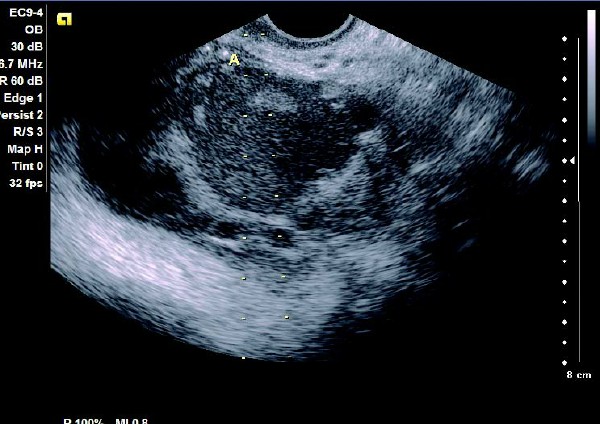

(1)单侧或双侧卵巢内呈现椭圆形或圆形无回声暗区,其内充满弱回声光点,囊肿直径一般为5~6 cm,大于10 cm 的较少见。

(2)壁较厚,囊内充满细小均匀点状回声,后方回声增强。

(3)常与周围组织有粘连,边界清晰。

患者,女,35岁。每次月经量少,痛经,近来行经期延长、疼痛加重来院诊治。超声报告显示子宫前倾位,子宫体大小为:5.9cm×5.1cm×4.8cm,形态规则,边界清晰,宫避回声匀称,宫腔线居中,内膜厚度0.6cm,宫内未见异常回声。右侧卵巢内可见大小约5.2 cm×4.9cm的无回声区暗区,壁厚,内壁欠光滑,内见密集细光点,边界清晰。CDFI探测囊壁及囊腔内无血流信号。

超声提示:右侧卵巢巧克力囊肿